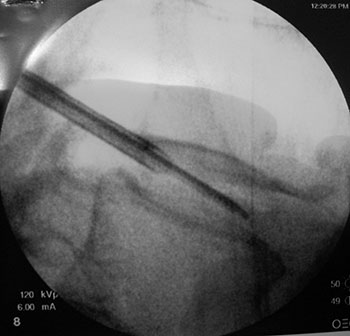

Após o diagnóstico foi instituído tratamento conservador com adequado por 7 meses, sem apresentar melhora do quadro, sendo então optado pelo tratamento cirúrgico com a hidrodiscectomia (Fig. 8).

Fig. 8a

Fig. 8b

Imediatamente após o procedimento a paciente já encontrava-se com remissão completa dos sintomas, e 1 ano após a realização do procedimento sem novas recidivas.